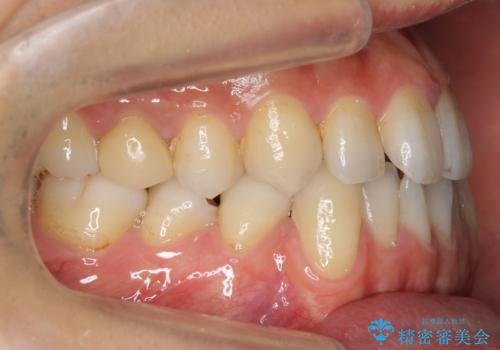

前歯の矮小歯 奥歯の反対咬合 をインビザラインで

- 上下の前歯が気になり来院。

左上2が矮小歯で小さく、また、左の奥歯が反対咬合になっていました。

左上2番はセラミッククラウンで反対側と同じ大きさにしました。

インビザラインでの臼歯の反対咬合の治療は難しいことが多いです。

今回は下の前歯を1本抜くことで、下の奥歯をしっかり内側に傾けて治療を行いました。